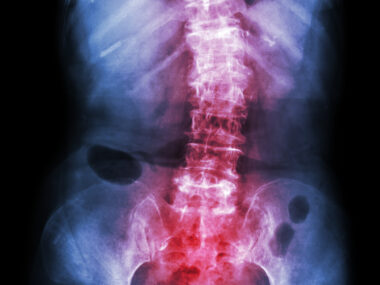

TNF inhibitors are medications that block the action of TNF, a protein that promotes inflammation and is abundant in the swollen, tender joints of people with arthritis such as ankylosing spondylitis, which is marked by inflammation in the spine.